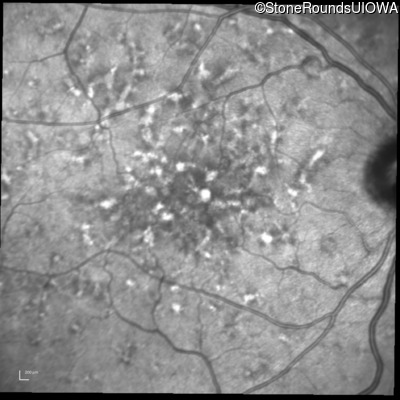

Blue Autofluorescence - Right - 20/20 -1

Exemplar